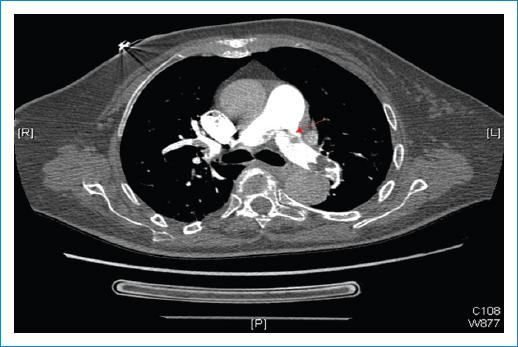

Una vez se trasladó la paciente a la unidad de cuidados agudos cardiológicos se le realizó ecocardiografía transtorácica (ETT), en la que se objetivaron trombos libres en las cavidades derechas, principalmente en la aurícula, y que protruían desde la vena cava inferior (Fig. 1). Se solicitó por este motivo una angiografía por TC con protocolo de TEP, en la que se objetivó TEP masiva bilateral (Fig. 2). Posteriormente, en una nueva ETT de control, se objetivó la presencia de un aneurisma del septo interauricular con aparente protrusión de la masa trombótica a través de este y que se extendía hacia la válvula mitral, y otra masa de aspecto trombótico en el tracto de salida del ventrículo izquierdo y la válvula aórtica (Fig. 3).

Figura 2 Angiografía por tomografía computarizada con protocolo de tromboembolia pulmonar que muestra embolia pulmonar «en silla de montar» (flecha).